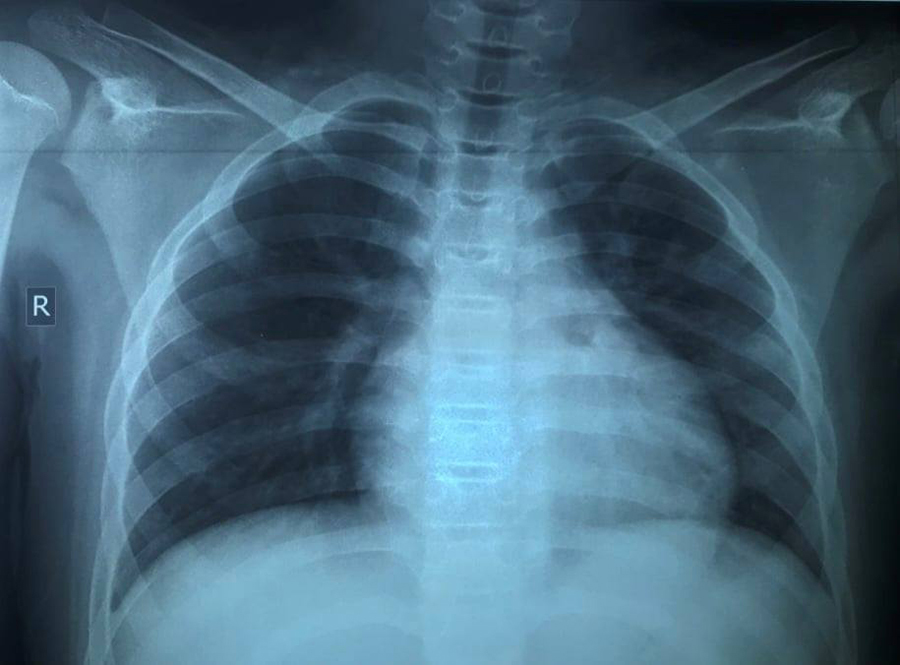

Theo các bác sĩ, dù triệu chứng bệnh không quá rầm rộ, kết quả X-quang khiến các y bác sĩ bất ngờ bởi phổi bé bị tổn thương nặng. Ngoài ra, các kết quả xét nghiệm cho thấy phản ứng viêm tăng cao, rối loạn đông máu.

Kết quả, sau 5 ngày điều trị, tình trạng bệnh nhi cải thiện tốt, hết khó thở, giảm ho nhưng tổn thương phổi trên X-quang cải thiện chậm, SpO2 còn thấp (93-94%).

Sau 17 ngày điều trị theo phác đồ đồng thời theo dõi sát triệu chứng và oxy máu, bé trai khỏi bệnh hoàn toàn, tổn thương phổi cải thiện đáng kể, xét nghiệm rRT-PCR cho kết quả âm tính.